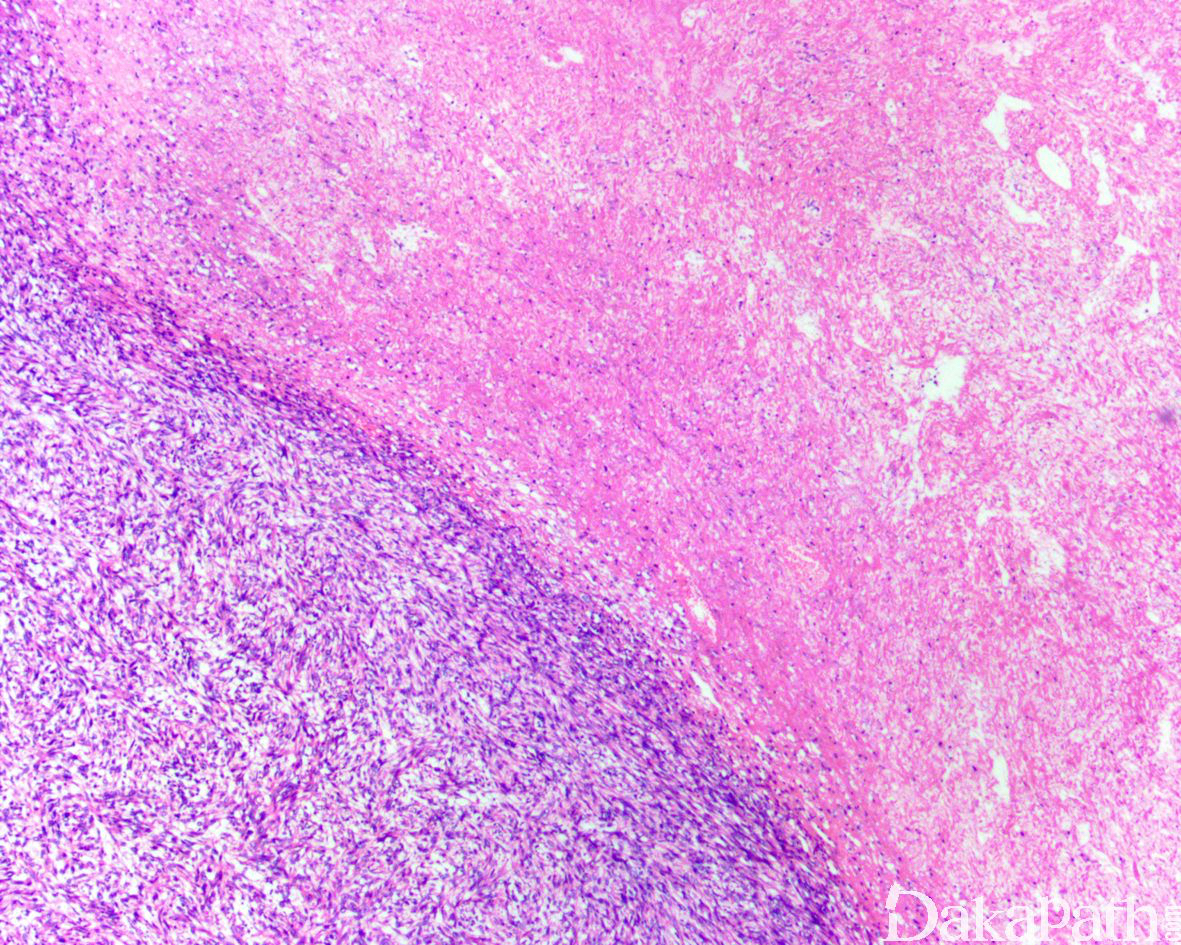

肿瘤细胞梭形,呈栅栏状、丛状或杂乱排列;

分化好的平滑肌肉瘤形态学上似平滑肌瘤,而分化差的平滑肌肉瘤形态学上具有多形性,核级别高,常见坏死和明显的核分裂活性。

判断其平滑肌分化的证据为背景中查见分化较好的平滑肌样细胞(包括原纤维状的嗜酸性胞质、两端顿圆的核以及胞质内的嗜酸性玻璃样小球等)。